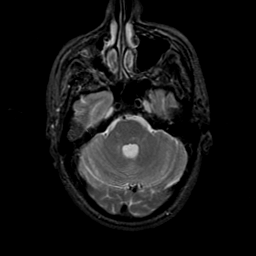

MR Study #23, January 26, 1992 -- Slice #13